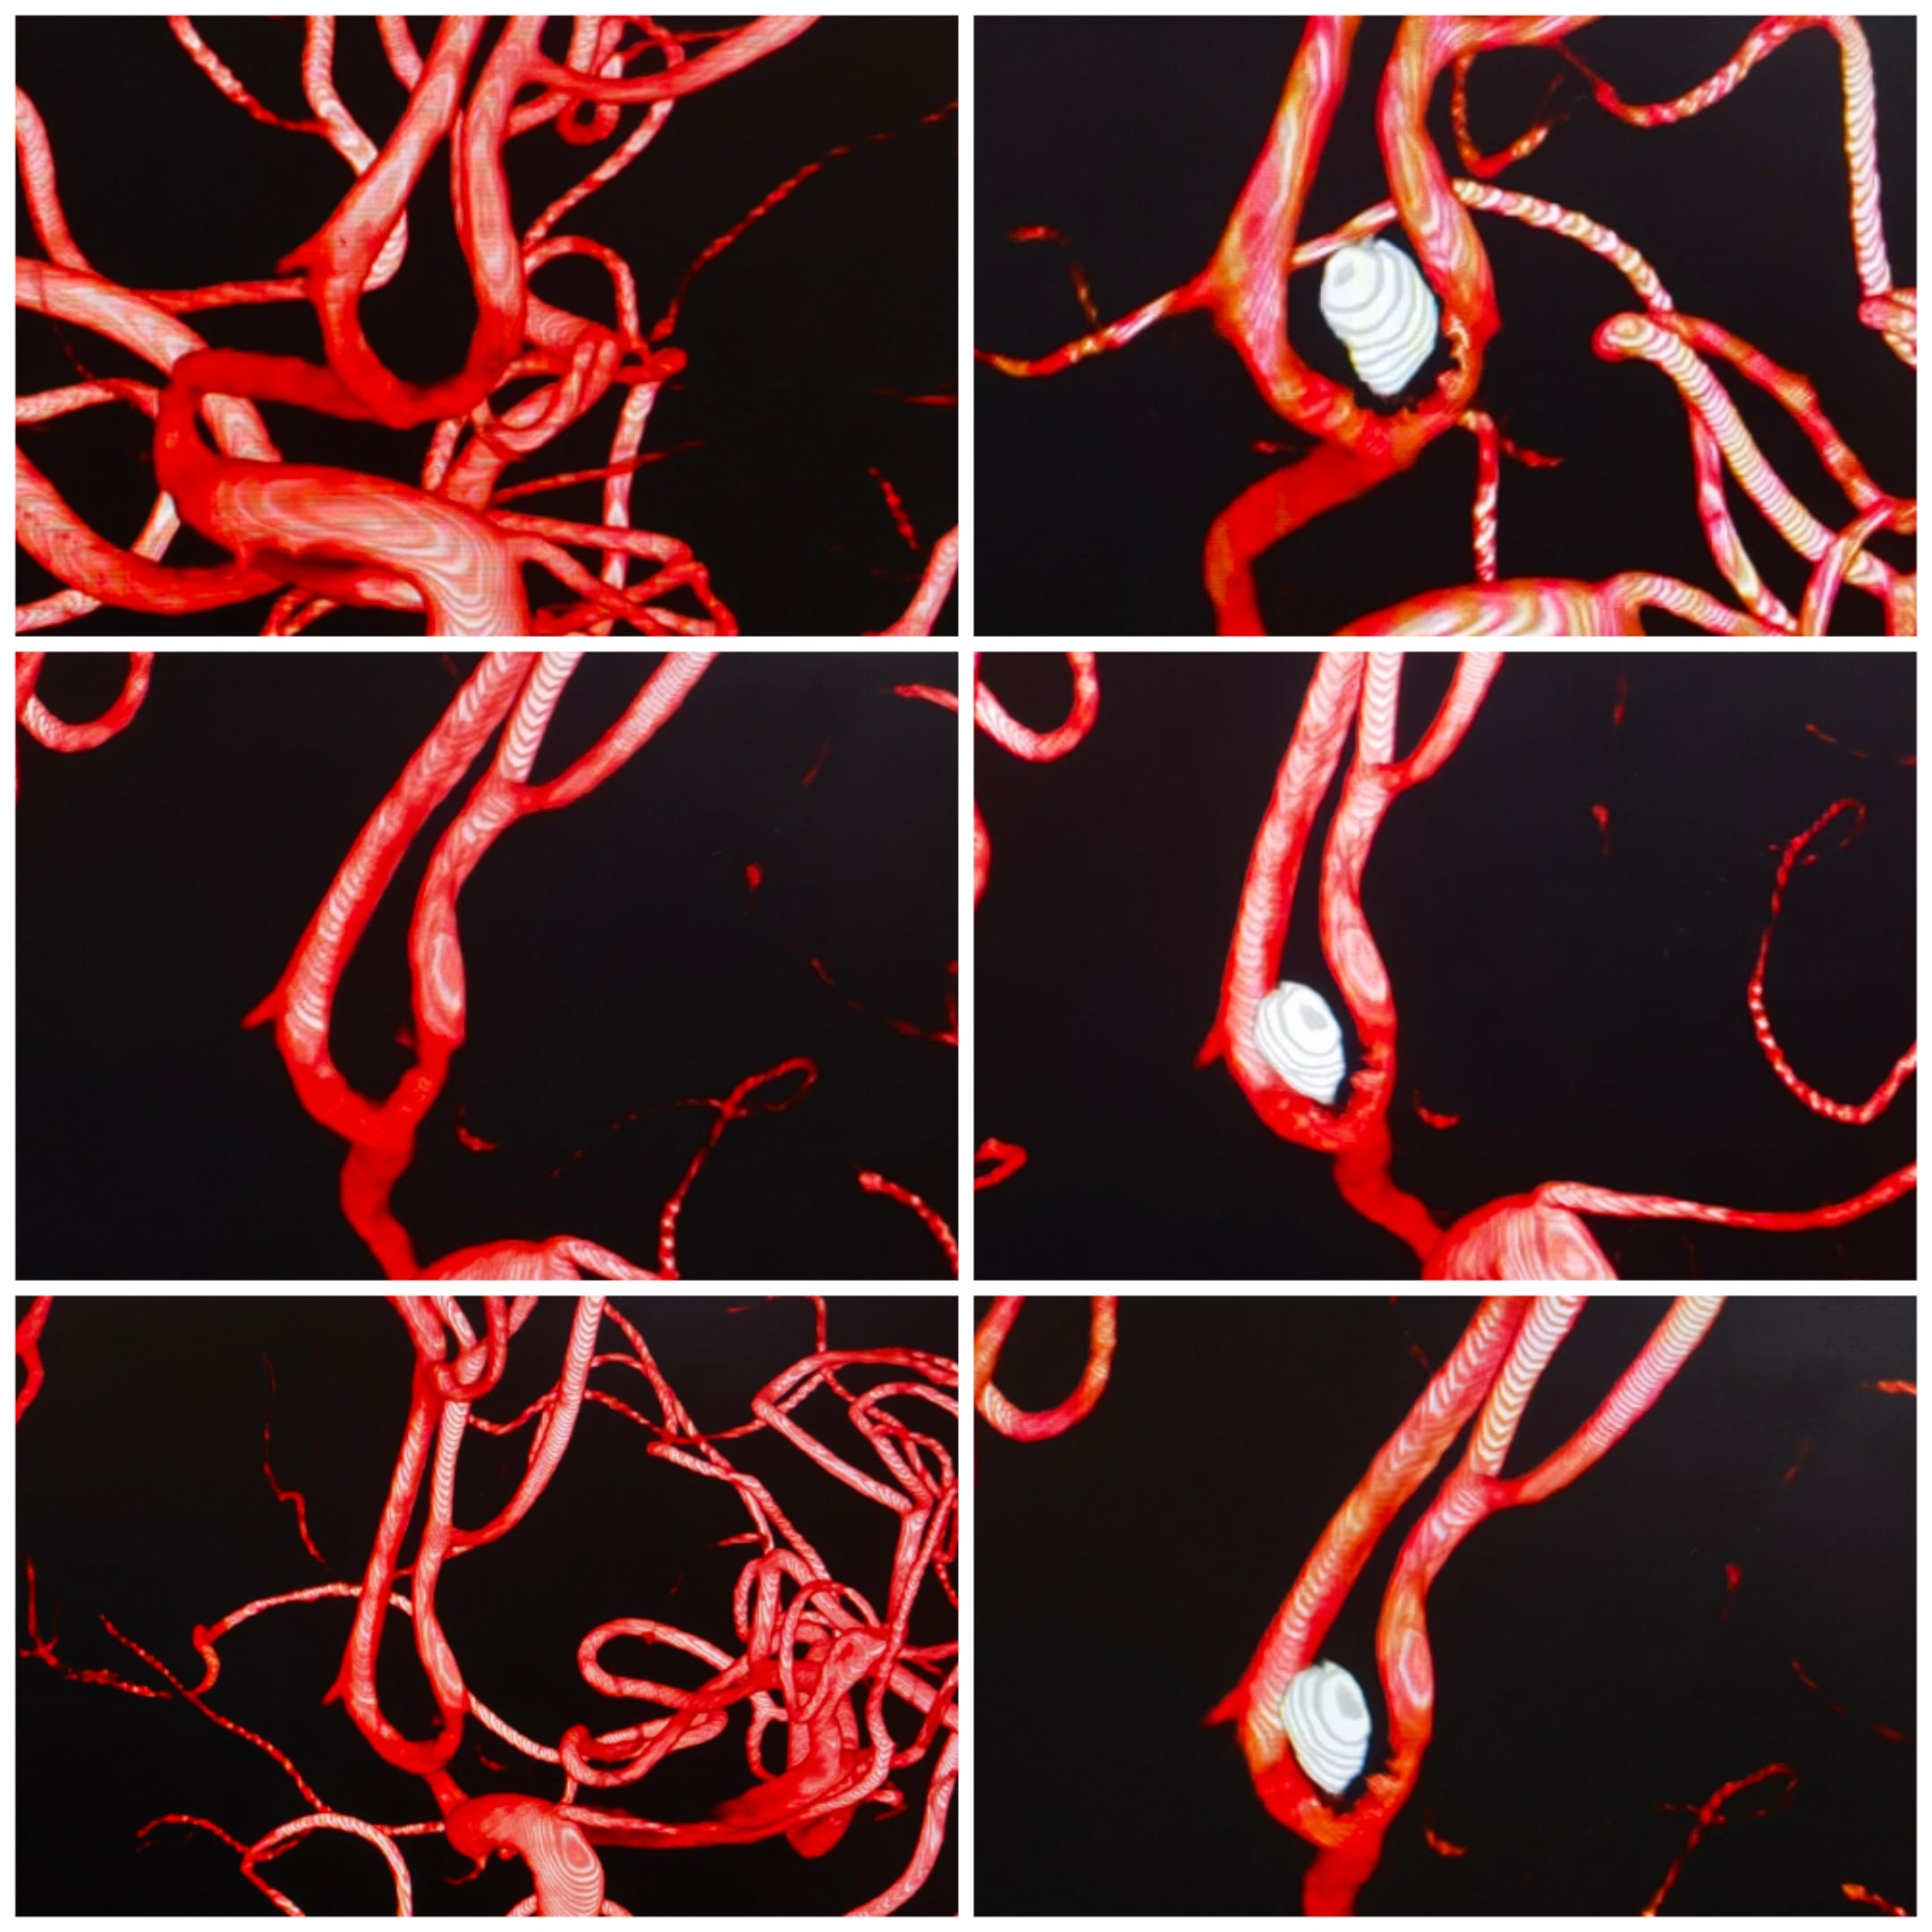

3D重建提示宽颈前交通动脉瘤,瘤颈偏向同侧A2。手术计划:支架置入同侧A2,利用开环支架穹窿效应保护对侧A2,行弹簧圈栓塞。WEB也是个不错的选择,可惜手上没有材料。

术后栓塞情况:支架开放良好,弹簧圈致密栓塞,双侧大脑前血流良好

术后3D重建情况

术后支架CT重建

双微管到达A2后,指引导管造影无法看到动脉瘤。经微管造影及路途,支架导管和栓塞微导管分别到位。选用开环支架穹窿效应缩窄瘤颈,保护对侧大脑前。

栓塞术后情况

术后重建情况